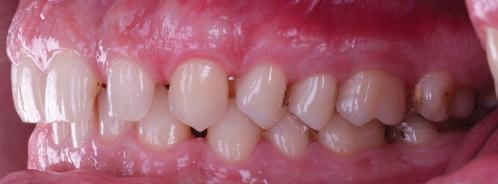

20 Dental Tribune Bulgarian Edition / октомври 2022 г. П ациентите със завършен растеж и скелетни проблеми обикновено представляват предизвикателство за ортодонт ската практика. Необходимостта от изваждане на зъби в комбинация с особеностите на възрастовата ортодонтия изисква особено внима ние. Фокусът върху критично важното значение на позицията на долните резци във връзка с дългосроч ната стабилност и постигането на оптимални оклузални взаимоотношения при затварянето на екстракционните пространства лесно може да излезе извън контрол. Когато към тези чисто кли нични проблеми се добави и стресът от натоваре ната практика, предизвикателството става още по-голямо. Всички тези фактори налагат използ ването на доказан подход с ясни и последовател ни стъпки, в което се разкрива силата на дисциплината „Алекзандър“ – предвидим протокол през целия процес на елиминиране на ротациите, ниве лиране на дъгите, затваряне на екстракционните пространства и финализиране на случая. Именно такъв е и случаят, който презентираме –екстракционен, скелетен клас 3 при възрастен па циент, лекуван по системата „Алекзандър“. ПРЕДВИДИМИ РЕЗУЛТАТИ ПРИ ПАЦИЕНТИ СЪС ЗАВЪРШЕН РАСТЕЖ И СКЕЛЕТЕН КЛАС 3, ИЗПОЛЗВАЙКИ ЕКСТРАКЦИОННО ЛЕЧЕНИЕ ПО ДИСЦИПЛИНАТА „АЛЕКЗАНДЪР“ Д-р Радой Димитров, България Преди започване на лечение клиничен случай | ортодонтия Фиг. 1а–1e Преди започване на лечение. Пациентът пристига в практиката с основното оплакване от невъзмож ност за нормално дъвчене. Снета е цялата необходима диагностична ин формация. Фиг. 1f–1h Снимки в профил и анфас. Фиг. 1i–1k Панорамна снимка, телерентгенография и анализ на телерент генография. Фиг. 1а Фиг. 1d Фиг. 1f Фиг. 1g Фиг. 1h Фиг. 1e Фиг. 1b Фиг. 1c Фиг. 1i Фиг. 1j Фиг. 1k

closed.

21Dental Tribune Bulgarian Edition / октомври 2022 г. ДИАГНОСТИЧНИ РЕЗУЛТАТИ: 1. Възраст на пациента: 21 години 2. Скелетен клас III (ANB 0) 3. Зъбен клас 3 4. Ръбцова захапка във фронта, кръстосана в дисталните участъци 5. Тясна горна челюст 6. Overjet – 0 мм, Overbite – 0 мм 7. Несъответствие на горната с долната средна линия 8. Единични контакти в ЦО 9. Хиподивергентен тип на растеж SN/MP – 33.5 10. Неравен гингивален контур 11. Неравна линия на усмивката 12. Тенденция за рецесии в долен фронт ПРЕПОРЪЧИТЕЛНО ЛЕЧЕНИЕ: Пълно ортодонтско лечение с метални брекети „Алекзандър“ Корекция на клас 3 захапката в областта на кучешките зъби с екстракция на първите пре молари в долна челюст Корекция на кръстосаната захапка в дистални участъци Коригиране на ръбцовата захапка във фронта Подобряване на ОJ и OB на пациента Стрипинг в долен фронт Подреждане на зъбите в горната и долната челюст Професионално хигиенизиране и профилактични дентални прегледи са препоръчителни на всеки 6 месеца. 1-ви месец След 1 месец са залепени брекети в горната челюст – поставена е еластична дъга. 016 NiTi. В долната челюст са елиминирани ротациите, поставена е стоманена дъга. 016SS, закалена с ток, и еластична верижка за затваряне на пространствата. 3-ти месец В долната челюст е поставена трета дъга – 17 x 25 NiTi с къси лигатури и верижка

В горната челюст се затварят пространствата с дъга .016SS и верижка. 5-и месец На 5-ия месец след залепяне на брекетите в долната челюст е поставена стоманена дъга 16 x 22 SS с четвъртито сечение, омега луп и тай бек. В горната челюст е поставена дъга 17 x 25 NiTi. Поради липсата на стабилни оклузални контакти са поставени лингвални верижки в областта на моларите, за да се предотврати нежелана ротация на 7-ите зъби. 6-и месец На 6-ия месец от началото на лечението са екстрахирани долните първи премолари, поставена е дъга 16 x 22 SS със затваряща чупка teardrop. Чупката се активира всеки месец по 1 мм с чинч-бек. клиничен случай | ортодонтия СТЪПКИ НА ЛЕЧЕНИЕТО Начало на лечението Лечението започва с поставяне на апарат за бърза експанзия в горната челюст. През първия месец от лечението са направени 24 оборота на апарата за експанзия. Залепени са брекети в долната челюст, поставена е дъга 17x25 CuNiTi, като са предпи сани клас 3 ластици (1/4”,4 1/2 oz) по време на сън, за да се осигури контрол върху торка на долните резци. Фиг. 2а Фиг. 3a Фиг. 4a Фиг. 3b Фиг. 4b Фиг. 3c Фиг. 4c Фиг. 3d Фиг. 4d Фиг. 3e Фиг. 4e Фиг. 5a Фиг. 5b Фиг. 5c Фиг. 5d Фиг. 5e Фиг. 6a Фиг. 6b Фиг. 6c Фиг. 6d Фиг. 6e Фиг. 7a Фиг. 7b Фиг. 7c Фиг. 7d Фиг. 7e Фиг. 2b Фиг. 2c Фиг. 2d

Dental Tribune Bulgarian Edition / октомври 2022 г.22 клиничен случай | ортодонтия 14-и месец В горната и долната челюст са поставени последни стоманени дъга с омега луп и тай бек – 17 x 25 SS с четвъртито сечение. Назначени е ластик за средната линия в комбинация с клас 3 ластик (1/4”, 6 1/2 oz). Контролни рентгенографии 13-и месец Екстракционните пространства са затворени. Направена е контролна панорамна снимка за оценка позицията на корените. Взето е решение за презалепване на брекетите на 12, 22 и пръстените на 36 и 46. 21-ви месец Средната линия в горната и долната челюст съвпадат. Ластиците са спрени. Свалени са пръстените и брекетите в горната и долната челюст, зигзаг ластици не са използвани поради благоприятните оклузални взаимоотношения. Фиг. 11j Ортопантомография в края на лечението. Фиг. 11k Телерентгенография след края на лечението. Фиг. 11l Анализ на телерентгенографията след лечението. Фиг. 11m Последователност на дъгите в горната и долната челюст Фиг. 11n Суперимпозиция на PreOp и PostOp ортопантомографии. 10-и месец Затварянето на пространствата е предвидимо и контролирано, без да се отварят пространства в зъбната дъга. Фиг. 8a Фиг. 8b Фиг. 8c Фиг. 8d Фиг. 8e Фиг. 10a Фиг. 10b Фиг. 10c Фиг. 10d Фиг. 10e Фиг. 9a Фиг. 9b Фиг. 9c Фиг. 9d Фиг. 9e Фиг. 9f Фиг. 11a Фиг. 11f Фиг. 11j Фиг. 11l Фиг. 11m Фиг. 11n Фиг. 11k Фиг. 11g Фиг. 11h Фиг. 11i Фиг. 11b Фиг. 11c Фиг. 11d Фиг. 11e

Dental Tribune Bulgarian Edition / октомври 2022 г. 23клиничен случай | ортодонтия реклама Лечението е продължило 21 месеца. Проведено е домашно избелване с индивидуални шини. За автора: Д-р Радой Димитров завършва с отличие Факултета по дентална медицина към МУ–София през 2015 г. В продължение на 5 години работи в няколко водещи практики в София, като през 2019 г. заедно със своята съпру га д-р Траяна Димитрова основават собствена практика в гр. Гоце Делчев –Dimitrovi Dental Care. Посещава редица курсове за повишаване на квалификаци ята, но най-сериозен тласък в развитието на ортодонтската си практика получава след завършването на комплексната ортодонтска програма, воде на от д-р Иван Горялов, базирана на дисциплината „Алекзандър“ – система с повече от 50 години опит в целия свят. Д-р Димитров е член на Българския изследователски клуб „Алекзандър“. Взе ма участие като гост-лектор в симпозиума с международно участие The Power of the Alexander Discipline, който се проведе на 14–15.05.2022 г. С д-р Ди митров можете да свържете на тел. +359885 252 025. Заключение Представеният случай е ярък пример за възможностите и красо тата на дисциплината „Алекзандър“ – приложен е утвърден под ход с ясни правила и са постигнати очакваните цели. Резулта тът ще бъде дългосрочно стабилен, тъй като са спазени всички правила, които се отнасят към максимално комфортната пози ция на зъбите в края на лечението. Постигнати са красива усмив ка и стабилна оклузия. ПОСТИГНАТИ РЕЗУЛТАТИ ОТ ЛЕЧЕНИЕТО 1. Коригирана ръбцова захапка 2. Коригирана клас 3 захапка в областта на ку чешките зъби 3. Коригирана кръстосана захапка в дисталните участъци 4. Коригиран овърджет и овърбайт 5. Разширена е горната зъбна дъга 6. Подредени зъби в горната и долната челюст 7. Постигната е стабилна захапка с множество контакти в ЦО 8. Драматично е подобрена дъвкателната функ ция 9. Подобрена е линията на усмивката ДРУГИ ПРОВЕДЕНИ ДЕНТАЛНИ ПРОЦЕДУРИ 1. Домашно избелване на зъбите 2. Екстракция на мъдреците Фиг. 12a Фиг. 12b Фиг. 12c Фиг. 12eФиг. 12d Фиг. 12f Фиг. 12g Информация за дати, цени и отстъпки www.bracescourses.com 0889 22 55 01 Практически курсове лектор д-р Иван Горялов Дисциплината „Алекзандър“ ПЪТЯТ КЪМ СУПЕРУСМИВКИТЕ 100% връщане на цялата сума, ако не сте удовлетворени след преминаване на Ниво 1 Директно и индиректно залепяне на брекети Анализ, диагноза и план на лечение Лечение на клас 2 дълбока захапка Екстракционно лечение Лечение на клас 3 отворена захапка НИВО 5НИВО 1 НИВО 2 НИВО 3 НИВО 4